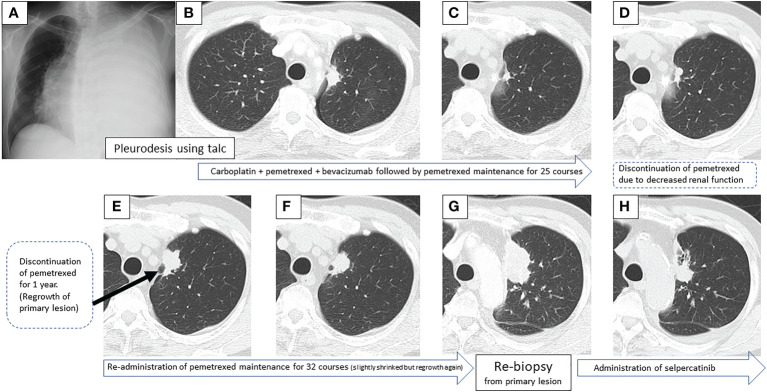

图1:在第一次就诊到开始进行第二次治疗期间,患者7年间原发病灶的顺序图像

一线治疗包括卡铂+培美曲塞+贝伐单抗,经过4个疗程后获得近乎有效缓解(CR),但鼻出血仍然持续,仅进行培美曲塞维持治疗。在维持治疗的25个疗程中实现了CR(图1C),但由于肾功能轻微恶化,治疗暂时中断。治疗结束后一年,CT显示原发病灶轻微进展(图1D),但反复速度较慢。确认CT反复一年后(图1E),重新开始培美曲塞单药治疗,原发病灶和淋巴结减小(图1F)。然而,在进行了32个维持治疗疗程后,出现了快速的全身进展。由于原发病灶再生(图1G)、对侧肺转移、多发性肝转移、右侧肾上腺转移和多发性脑转移(图2A、B),需要调整他的治疗方案。

通过支气管镜对原发病灶进行再活检,细胞学评估显示V级腺癌,组织学评估证实了这一结果。肿瘤正确用药850基因检测确认患者为RET融合基因阳性,随后于第二天给予240mg塞尔帕替尼。第13天的CT显示与基线影像相比(图1H),所有转移病灶,包括脑转移(图2C、D),均有良好的全身反应。由于2级肝酶升高,继续给予剂量减少的塞尔帕替尼(每天160mg)。使用高敏感度的下一代测序(NGS)面板系统:肺癌紧凑面板,并使用细胞学刷液进行RNA检测,证实了融合基因KIF5B外显子15;RET外显子12(K15RET12)。肿瘤正确药基因解码基因检测还能够从7年前的胸腔积液细胞块的福尔马林固定石蜡包埋(FFPE)标本中进一步确认RET(图3A、B),这些标本在恶性细胞的形态学上与再活检样本相似,具有大核仁(图3C、D)。从初始细胞块样本中收集到的RNA(1256ng)具有RNA整合数(RIN)值为4.8。单重PCR和NGS检测均检测到了K15RET12融合峰(图3)。